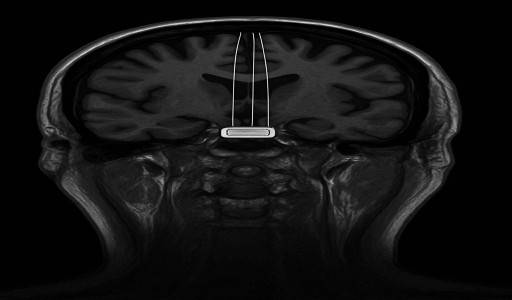

وتحمل الشريحة اسم “Telepathy” (تيليبيثي)، وهي الجيل الأول من واجهات الدماغ والحاسوب التي طورتها "نيورالينك"، وتعمل عبر التقاط الإشارات العصبية من خلايا الدماغ وتحويلها إلى أوامر رقمية يمكن للأجهزة الإلكترونية تفسيرها وتنفيذها بدقة عالية.

وقال جيمس، الذي يعاني من شلل نصفي، إنه استطاع تحريك المؤشر على شاشة الحاسوب وتنفيذ أوامر بسيطة "بقوة التفكير فقط"، واصفًا التجربة بأنها "تحول جذري في قدرات الإنسان على التواصل دون حركة".